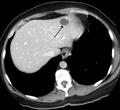

- A liver hemangioma as seen on CT